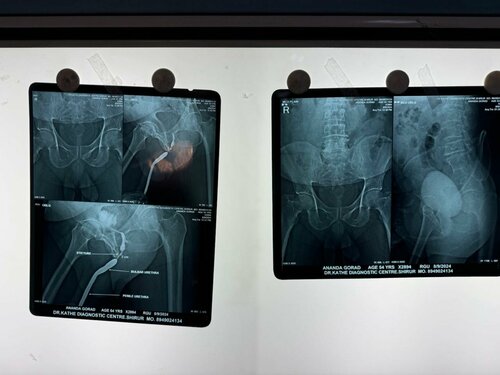

Expert Urethral Stricture Treatment by Dr. Bhoopat Bhati | Urologist in Viman Nagar

A bulbar urethral stricture is a narrowing of the urethra, the tube that carries urine out of the body, in the bulbar region (near the ...